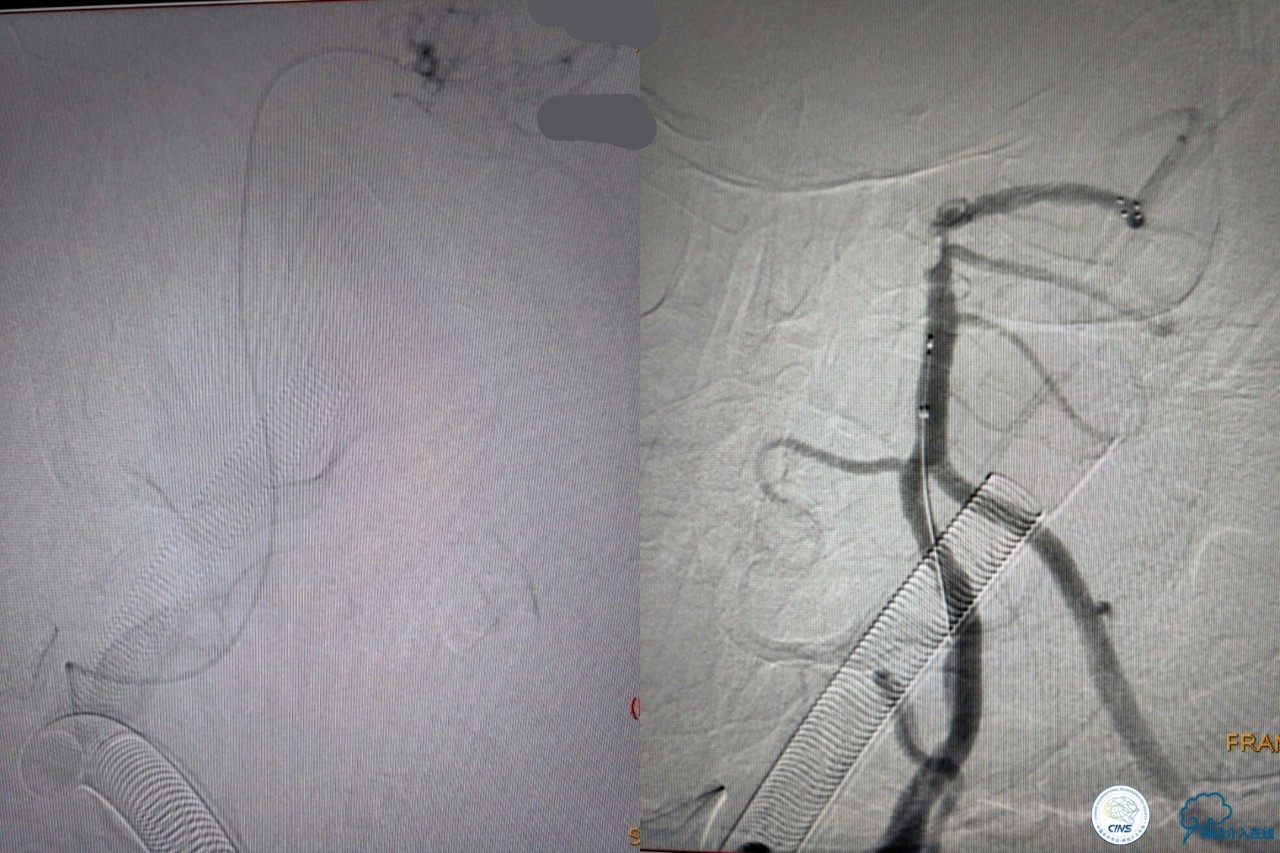

造影结果:右侧颈总动脉远端闭塞,前交通动脉开放,代偿方式:左侧颈内动脉→左侧大脑前动脉A1→前交通动脉→右侧大脑前动脉A1(反向)→右侧大脑中动脉供血区代偿。双侧大脑后动脉、右侧小脑上动脉及基底动脉顶端未见显影。

结合病史,体征及影像学,考虑患者本次发病为基底动脉尖急性闭塞,发病机制:栓塞?右侧颈总动脉慢性闭塞?非责任血管,且代偿良好,暂时不需处理!

6F导引导管到位至RV2远端,rebar-18微导管及transand微导丝至右侧大脑后动脉P1远端。

solitaireAB4-20mm支架取栓。